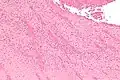

| A recent pulmonary thrombo-embolus with prominent lines of Zahn. The pale areas consist of fibrin and platelets. The red areas consist of erythrocytes. | |

Lines of Zahn are a characteristic of thrombi.[1] They have visible and microscopic alternating layers (laminations).[2][3] Platelets mixed with fibrin form lighter layers.[2] Red blood cells form darker layers.[2] Sometimes, the term "lines of Zahn" only refers to the lighter layers.[4]

Lines of Zahn can be used to confirm diagnosis of a thrombus.[1] Their presence implies thrombosis at a site of rapid blood flow that happened before death. They are more common in thrombi formed in the heart or aorta.[5] In veins or smaller arteries, where flow is not as constant, they occur less frequently.[5] They are also only seen on thrombi formed when blood is flowing. This is a distinguishing marker between thrombi that formed before death and after death.